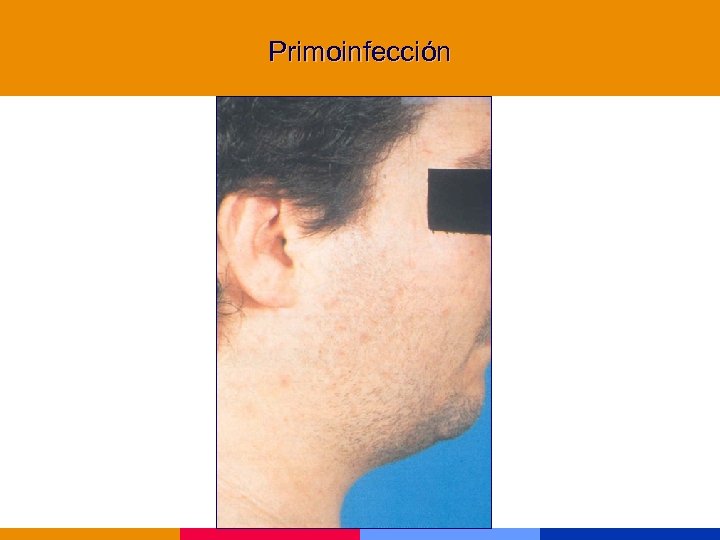

Primoinfección

Primoinfección

Primoinfección

Primoinfección

Primoinfección

Primoinfección

Primoinfección

Primoinfección